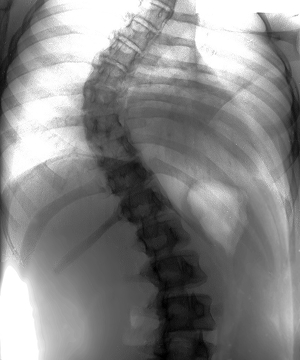

척추측만증

• 척추측만증은 척추가 정상적으로 반듯해야 하지만, 앞에서 볼 때 C자나 S자 형태로 휘어져 있는 상태를 말합니다.

이로 인해 척추 부위에 하중이 집중되고 통증이 발생할 수 있습니다. 최근에는 학생(청소년)들 사이에서 많이 발생하고 있으며,

장기간의 바르지 않은 자세가 습관화되면서 그 빈도가 증가하고 있습니다. 조기에 발견하면 교정 치료를 통해 효과적으로 치료할 수 있습니다.

• 증상

• 허리를 굽혀 등의 높이를 보았을 때 양쪽 등의 높이가 다른 경우

• 양쪽 어깨 높이가 다르거나 양쪽 골반의 높이가 다른 경우

• 양쪽 다리의 길이가 차이가 나는 경우

• 갈비뼈가 비대칭을 이루거나 어깨 부위 날개뼈가 튀어나오는 경우

• 양쪽 가슴의 크기가 다르거나 등의 굴곡이 불균형을 보이는 경우

척추측만증 예시 사진